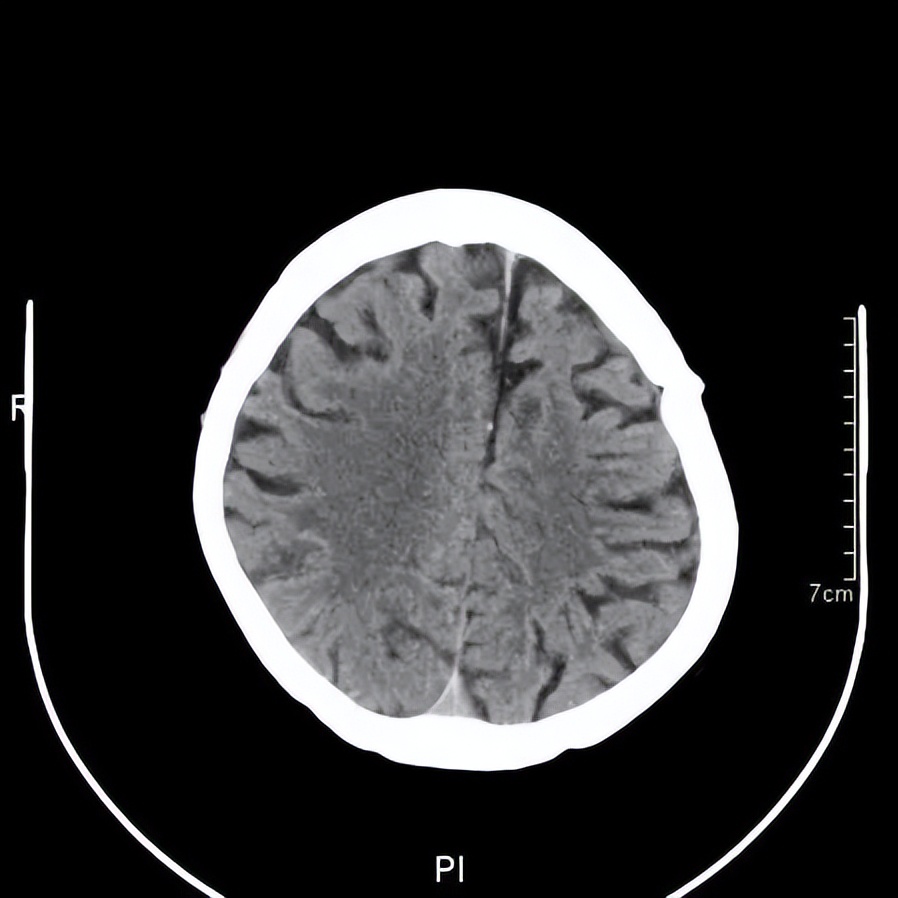

黄主任询问了王阿婆的病史,给她做了简单的神经检查和认知测试,给王阿婆安排了急诊CT检查。结果显示,王阿婆的脑部有两处出血,报告为“双侧慢性硬膜下血肿”,需尽快神经外科住院治疗。神经外科建议王阿婆接受一个叫做“双侧钻孔引流”的手术。需在王阿婆的头部钻两个小孔,把血肿引流出来,手术并不复杂,但是需要专业的神经外科医生来执行。

王阿婆门诊的头颅CT